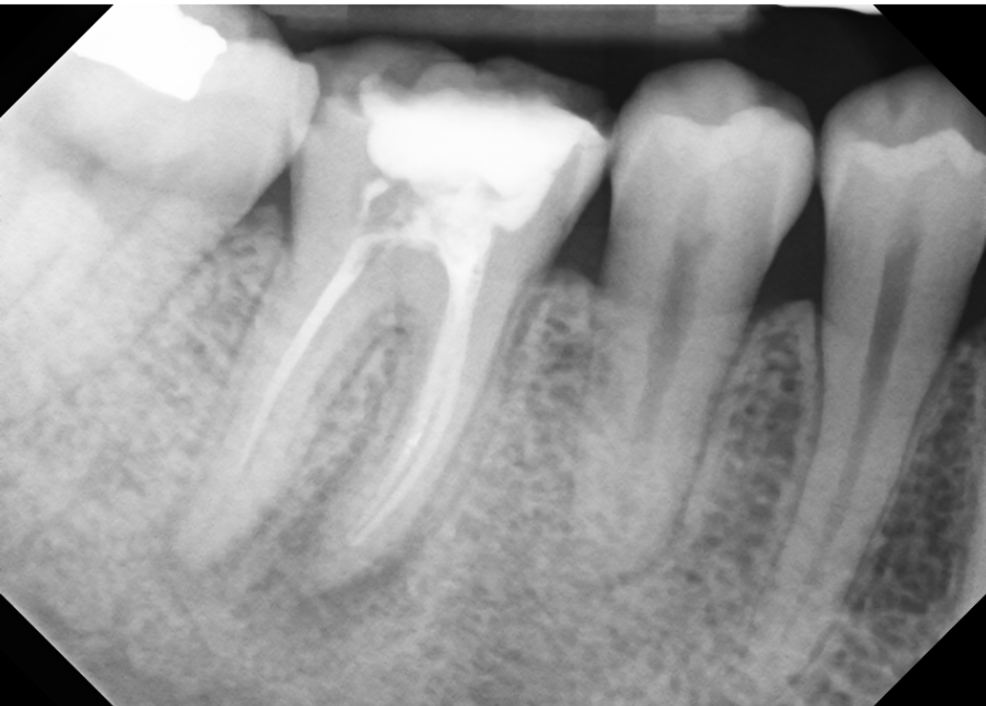

Pre Op #30

Patient presented for retreatment of tooth #30

(+)perc, (-)palp, previous RCT

CBCT scan taken, (+)PAP MB root, short fill on mesial and distal roots

#30

Apical: symptomatic AP

Pulpal: previously treated

Retreatment was completed in two visits, patient felt great after first visit.

Retreatment was uneventful.